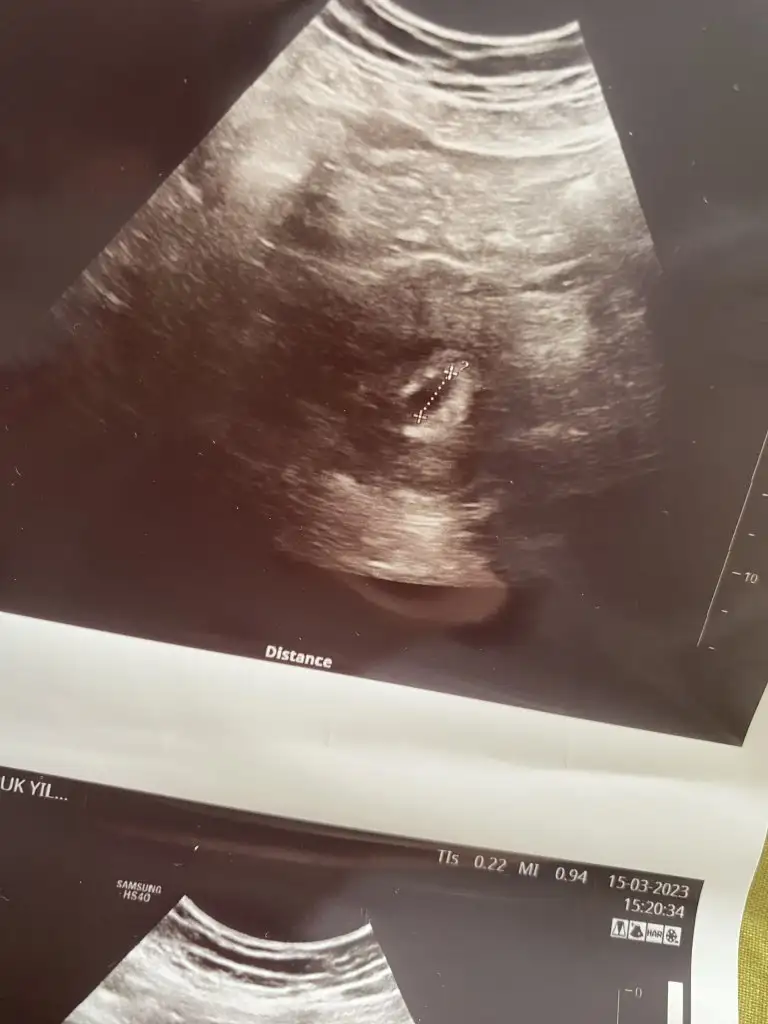

Güzel anneler bebeğinin kalp atışını duyan var mı?? Ben önümüzdeki Çarşamba kalp atışıni duymaya gidicem ve 7+6 haftalık olucam o vakit. Çok korkuyorum duyamam diye ve bebek görünür mü ki. Ya da sadece yolk kesesi olarak mı görünür? Bilgisi olan var mı??